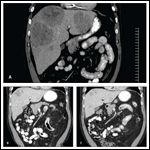

FIGURE 4

CT Coronal Images of the Metastatic Liver Lesions

The patient was started on sirolimus at 0.25mg/m2/day, with subsequent dose increases to achieve a target trough level between 15 and 20 ng/mL. One month after initiating sirolimus, the patient was titrated up to a dose of 2 mg daily. His transfusion-dependent anemia resolved, as did his symptoms of fatigue, dyspnea, nausea, anorexia, and abdominal pain. He was able to go back to work and able to travel. On restaging CT scans 2 months after starting treatment, he had a marked reduction of all his hepatic lesions, some by more than 50% (Figure 4A and 4B). There was no evidence of new disease and no change in the previously noted tiny 2- to 3-mm pulmonary nodules. Restaging CT scans at 4 months showed no further decrease in the size of the hepatic lesions, but continued disease stability (Figure 4C). At the present time, he continues on sirolimus at 3 mg per day and is tolerating treatment well.